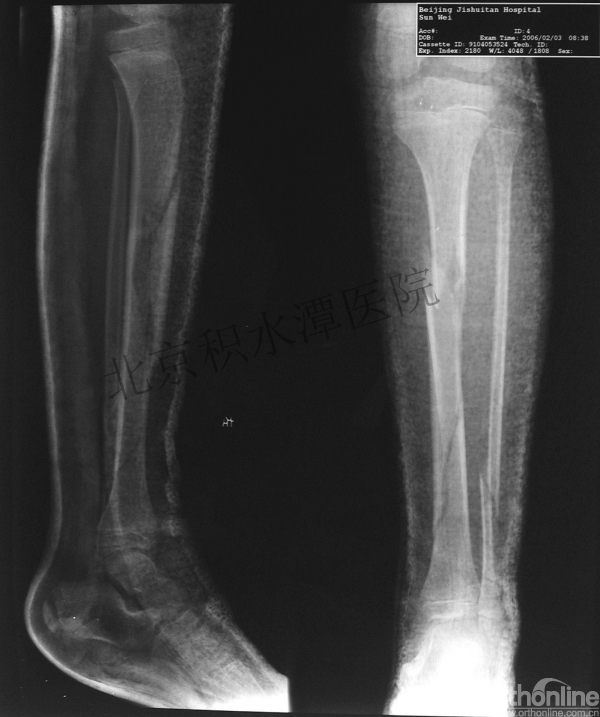

女孩、6岁,股骨干骨折

原始损伤

牵引后4周

伤后18月

没有任何外观和功能障碍!相信每位小儿骨科医生都会有很多类似的病例!除非您不承认或者没有认识到塑形!